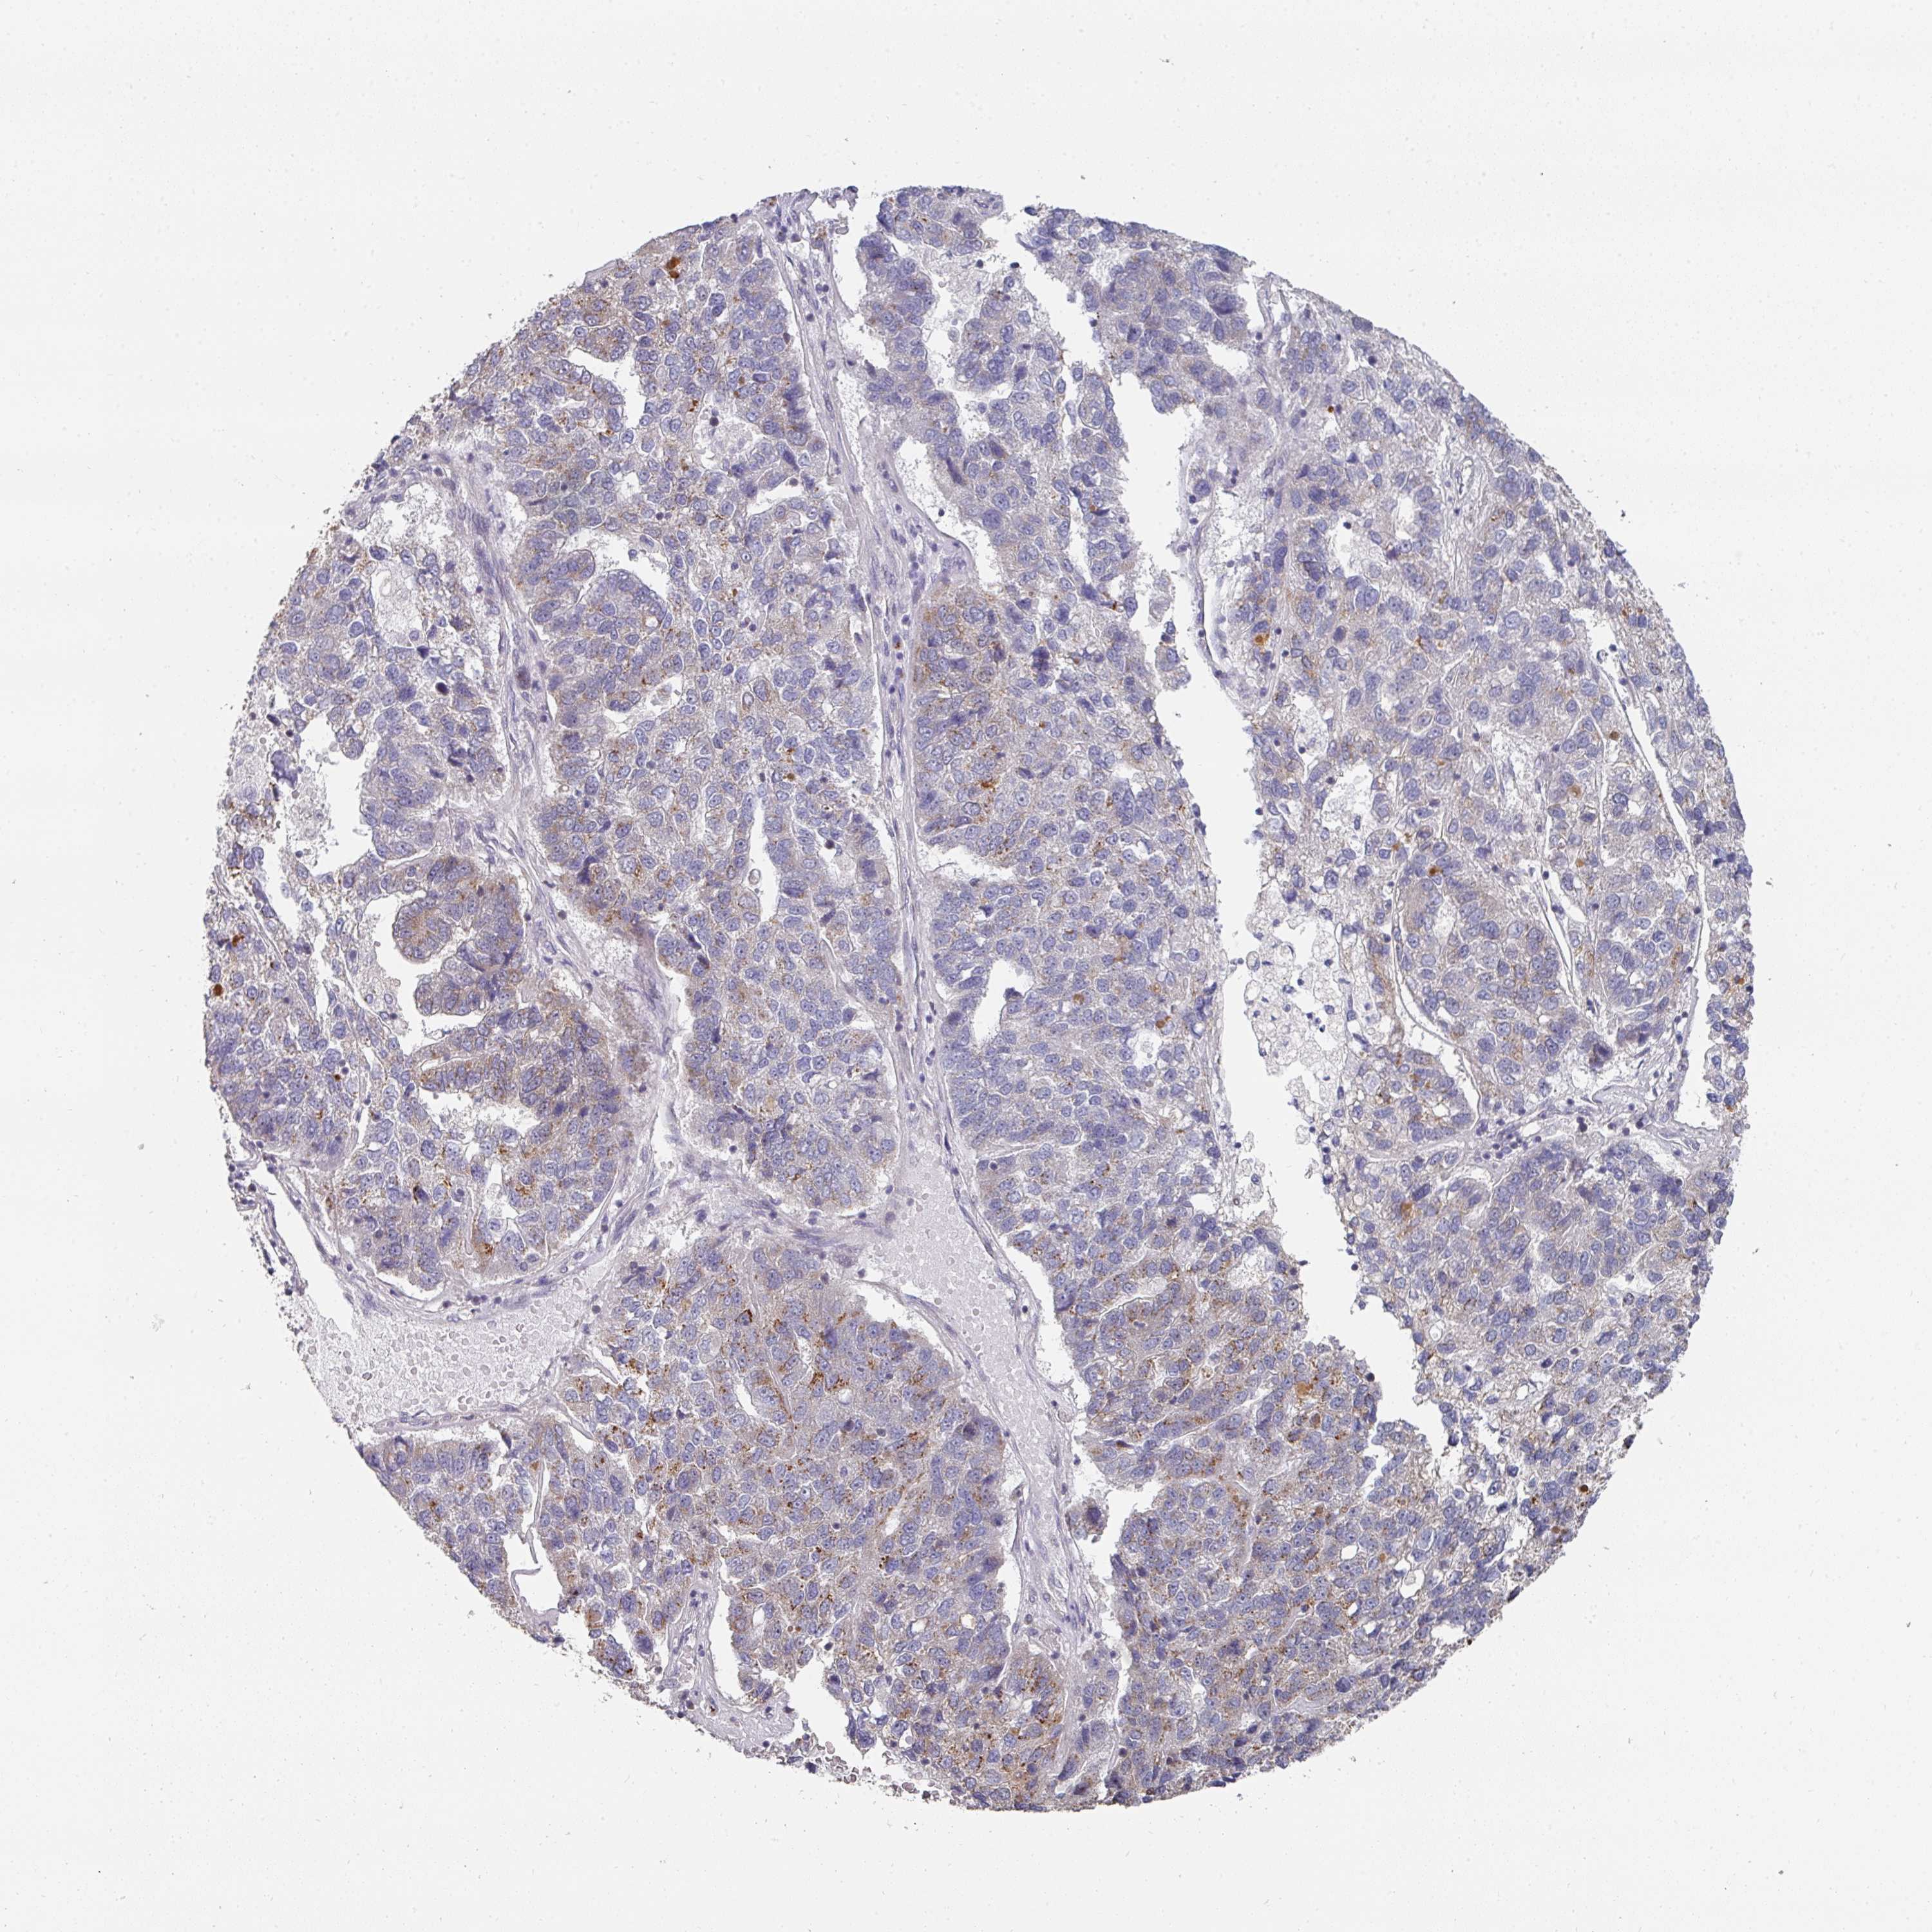

PANCREATIC CANCER - Protein expressioni

A mouse-over function shows sample information and annotation data. Click on an image to view it in a full screen mode. Samples can be filtered based on level of antibody staining by selecting one or several of the following categories: high, medium, low and not detected. The assay and annotation is described here.

Note that samples used for immunohistochemistry by the Human Protein Atlas do not correspond to samples in the TCGA dataset.

Antibody stainingi

Antibody staining in the annotated cell types in the current human tissue is reported as not detected, low, medium, or high, based on conventional immunohistochemistry profiling in selected tissues. This score is based on the combination of the staining intensity and fraction of stained cells.

Each image is clickable and will lead to virtual microscopy that enables deeper exploration of all samples and also displays staining intensity scores, fraction scores and subcellular localization as well as patient and tissue information for each sample.

Antibody HPA051314

Staining

High

Medium

Low

Not detected

Intensity

Strong

Moderate

Weak

Negative

Quantity

>75%

75%-25%

<25%

None

Location

Nuclear

Cytoplasmic/membranous

Cytoplasmic/membranous,nuclear

Adenocarcinoma, NOS